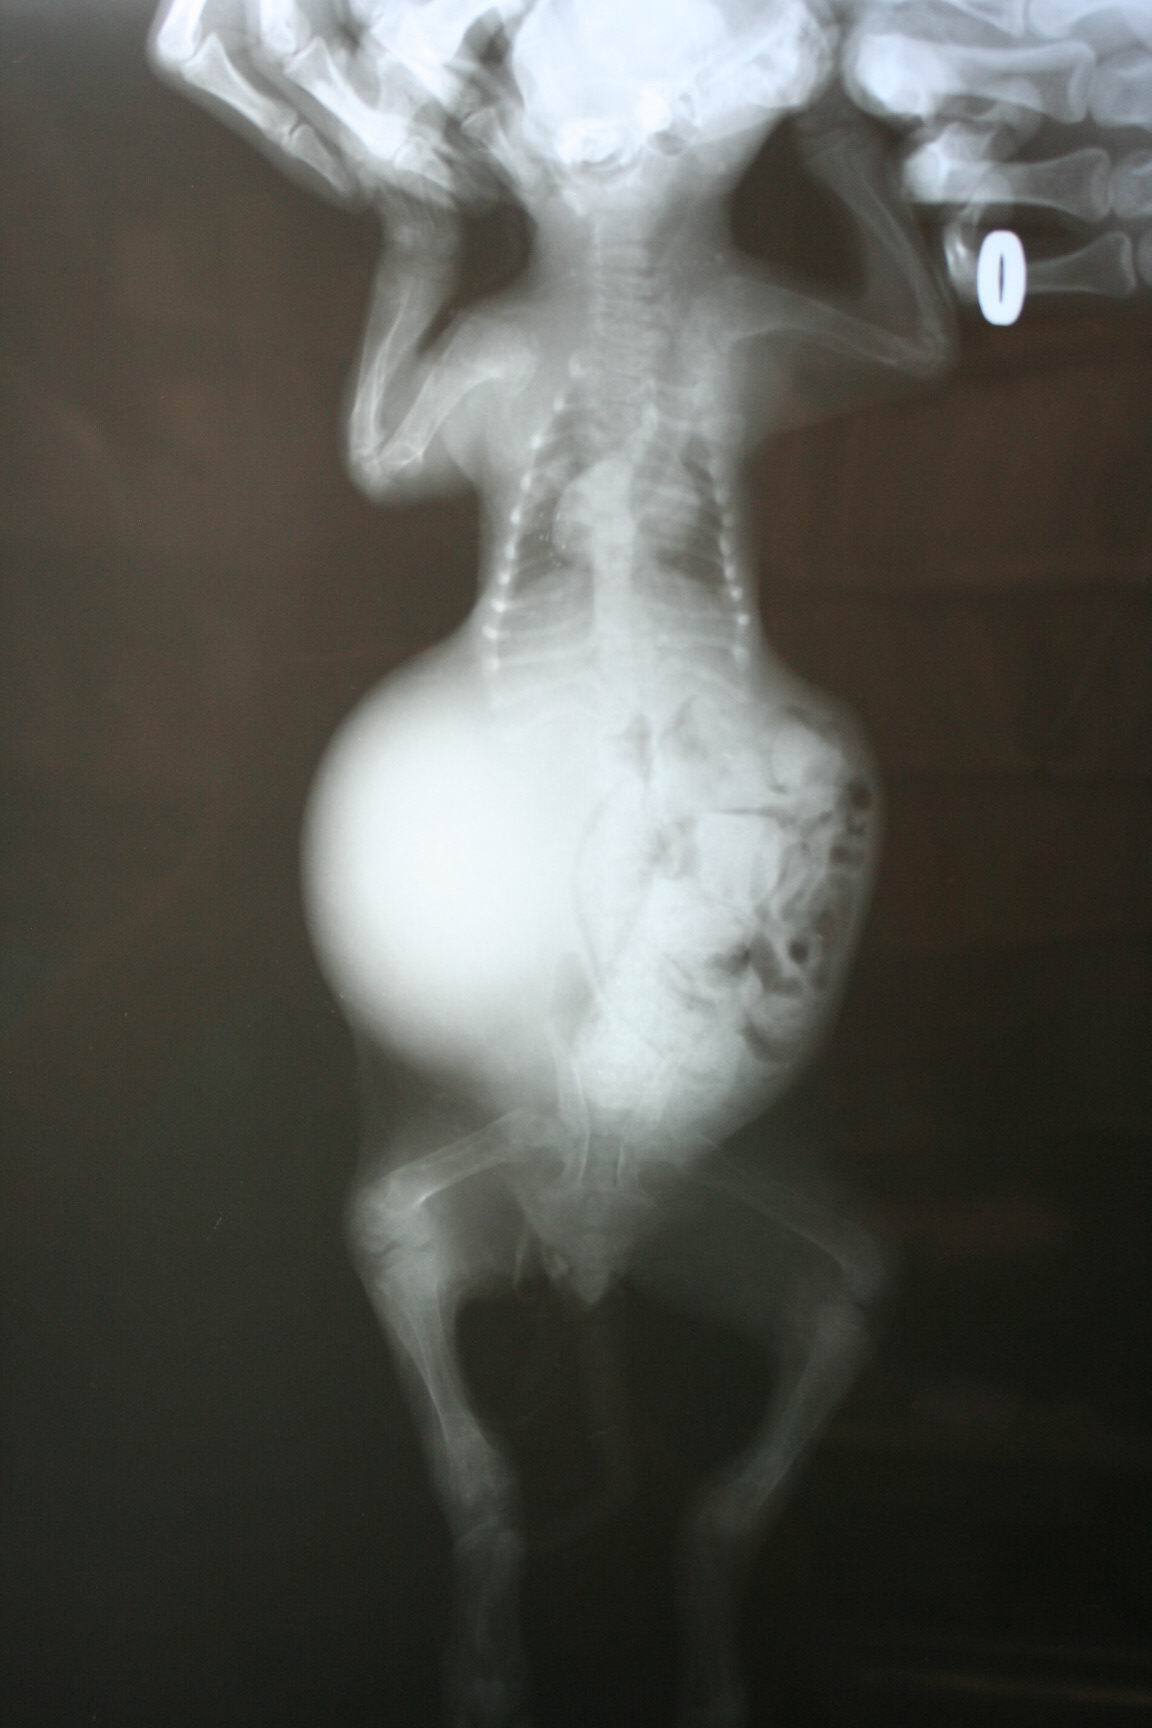

醫生診斷∼可能是車禍或是外力所造成..第11-13胸椎有斷裂..第2-3 腰椎有斷裂..無法自行排便及排尿..已先幫助擠尿及通便.針灸治療..目前出院瑤媽接手後續照護..小橘子好乖.雖然生病還是一直呼嚕.愛抱抱.請大家幫幫忙.慷慨解囊..小橘子還小.希望能熬過這關卡...感謝大家.感恩^^~

5.1/18∼X光片2張400X2= 800

6.1/19∼X光片2張400X2= 800

( 再次 確診大便 排出 及脊椎 斷裂處)